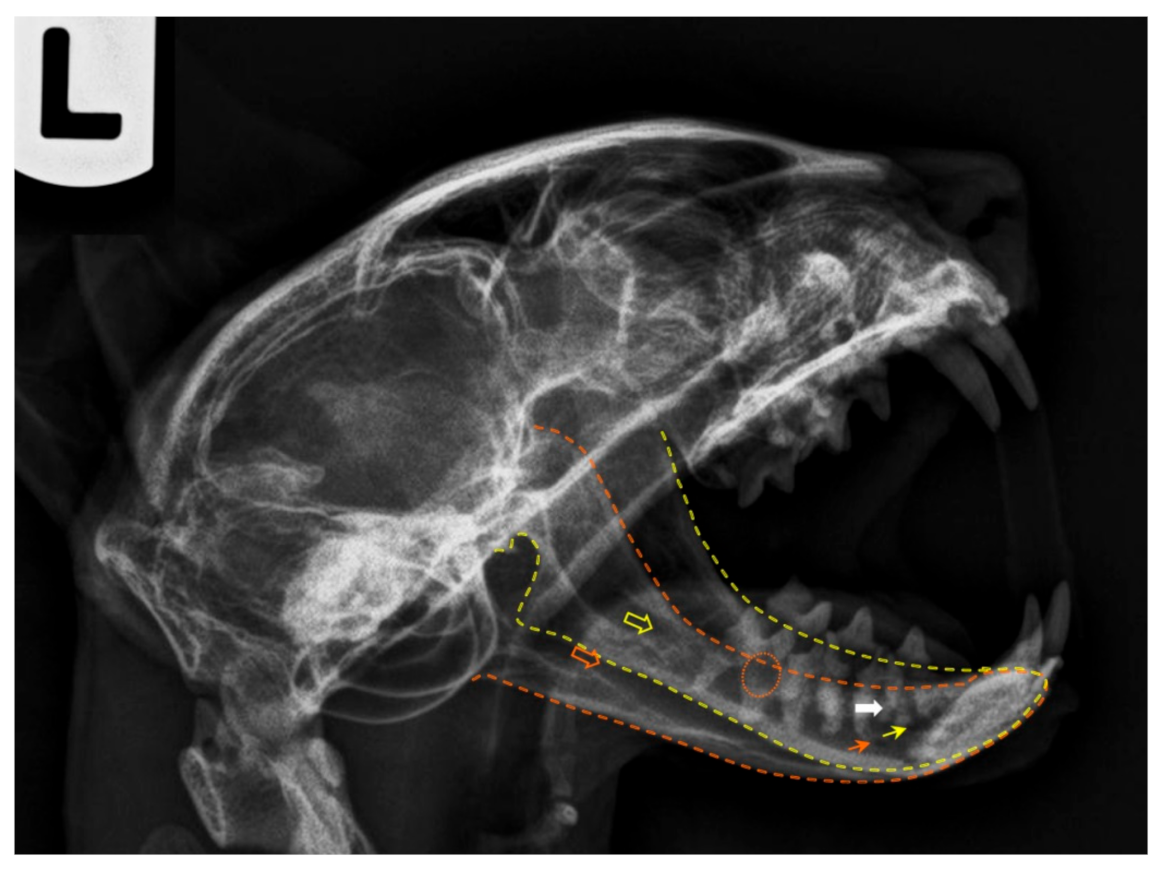

Kilitli çene sendromu hem kedilerde hem de köpeklerde meydana gelebilir. Her iki türde de genellikle travmaya bağlı bir öykü yaygındır. Tek taraflı olgularda, genellikle alt çene diğer tarafa doğru hafifçe kaymıştır. Ağzını açamayan ya da kapatmaya isteksiz olan hayvanlar öncelikle fiziksel olarak çok iyi muayene edilmelidir. Bu fiziksel muayene esnasında yüz, göz, çene ve kafatası kemikleri de dikkatli biçimde değerlendirilmelidir. Fiziki muayeneden sonra çene ve diğer kranial kemiklerin radyolojik incelemesi yapılmalıdır. Bu inceleme esnasında çekilen röntgen pozları özel pozisyonlarda verilmesi gerektiği için konuda deneyimli hekimler tarafından uygulanmalıdır. Röntgenin yeterli olmadığı durumlarda bilgisayarlı tomografiden de yararlanılabilir.